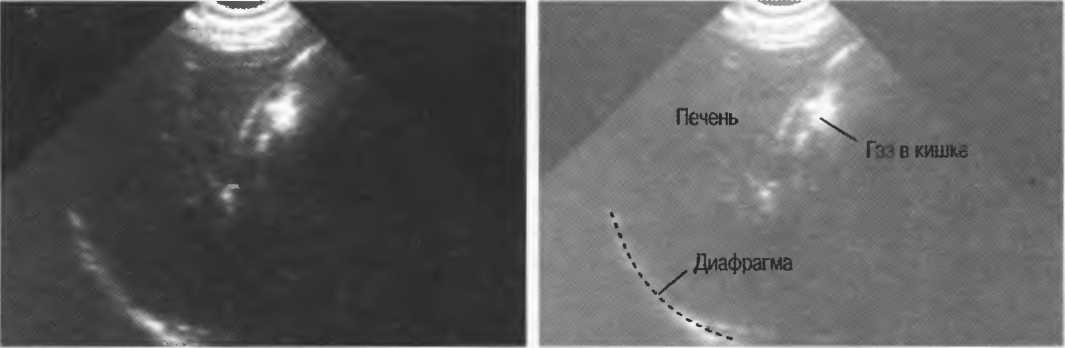

Рис.6. Сагиттальный срез печени: имеется очень сильное (зеркальное) отражение от диафрагмы, являющейся таким мощным отражателем, что изображение печени повторяется за ней. Ультразвуковые волны проходят через печень после излучения, затем повторно — после отражения от диафрагмы, затем — от поверхностей тканевых структур.